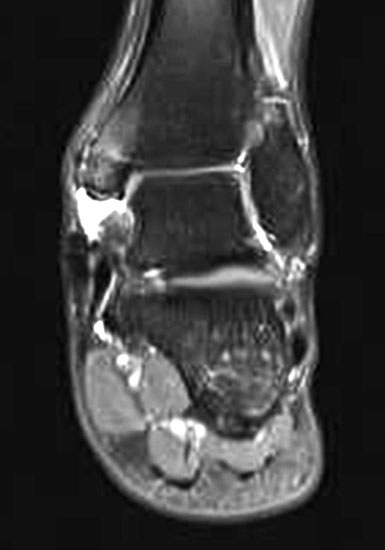

Aufgrund der geringen Zuverlässigkeit der klinischen Untersuchung und der konventionell radiologischen Bildgebung ist die Bildgebung der Wahl die Kernspintomographie (Szeimies 2014). Allerdings bestehen auch bei der Kernspintomographie klare Grenzen, vor allem hinsichtlich der Beurteilung der mechanischen Stabilität. Zuverlässige Aussagen sind möglich zum Ausmaß der Verletzung, insbesondere welche Bandanteile betroffen sind, sowie zu Begleitverletzungen. Chun et al. 11 berichteten über eine Sensitivität von 84% und eine Spezifität von 93,5% für Läsionen des Deltabandes im MRT. Befunde im MRT umfassen eine flächige Ödematisierung und Einblutung entlang des Deltabandes, meist unter Aussparung der kräftigen Pars tibiotalare posterior. Ein gewellter Verlauf, sowie eine Unterbrechung der Kontinuität der Faszikel sind Zeichen eines strukturellen Schadens. Teilweise finden sich Knochenkontussionsödeme, aber auch kortikale Absprengungen am lateralen Talusrand, der Talusschulter und am Außenknöchel. Fast immer findet sich ein Gelenkerguss (Abbildung 4).

Die zuverlässigste Beurteilung der mechanischen Stabilität des Deltabandes gelingt durch die diagnostische Arthroskopie (Abbildung 5)13.

Da bei der medialen Instabilität Befunde der MRT-Untersuchung entgehen können, wird bei Verdacht auf eine chronische Instabilität die ergänzende Arthroskopie empfohlen 13. Die dynamische Untersuchung des Sprunggelenks unter arthroskopischer Sicht ermöglicht die derzeit beste Beurteilung der Stabilität der medialen Bandstrukturen. Getestet wird die mediale und laterale vordere Schublade, die mediale und laterale Aufklappbarkeit, die Stabilität der Syndesmose und die generelle Laxizität des Gelenks durch axialen Zug. Neben der Stabilitätsbeurteilung ermöglicht die Arthroskopie eine Beurteilung der verletzten Strukturen, die Synovektomie mit Entfernung von freien Gelenkkörpern und die Abtragung von Osteophyten (Abbildung 7).